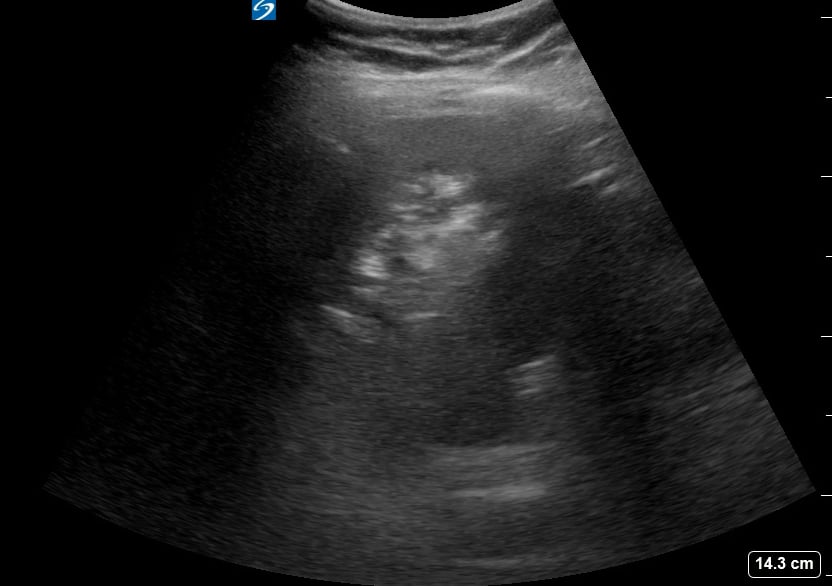

The “curtain sign” in lung ultrasound describes the progressive disappearance of lung tissue from view as the aerated lung expands during inspiration, obscuring deeper structures. This phenomenon resembles a curtain drawing across the screen, indicating normal lung aeration and pleural sliding. It’s a key positive finding, differentiating normal lung from pathologies like pleural effusion or consolidation.

In medical ultrasound, recognizing the curtain sign is vital for accurate diagnosis and patient management. Its presence helps clinicians confirm adequate ventilation in the examined lung region. This acoustic artifact is highly relevant in point-of-care ultrasound (POCUS) to quickly assess lung health and rule out significant pleural or parenchymal abnormalities.